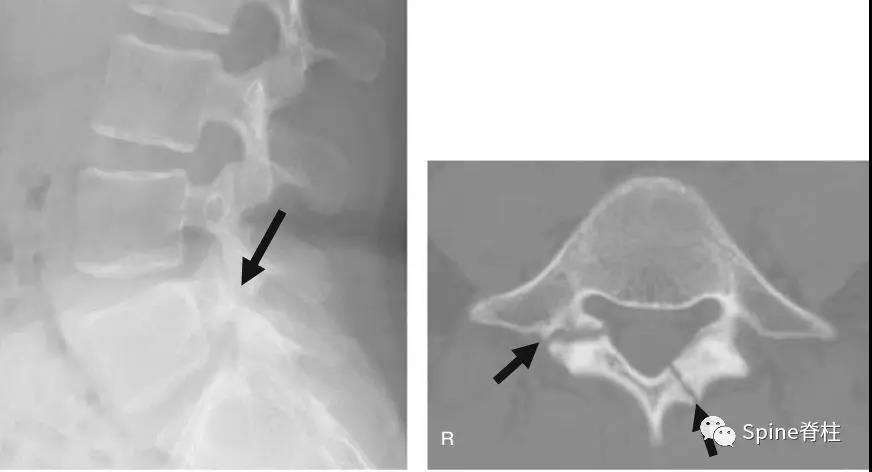

椎弓根钉误置引起的迟发性术后神经损害

椎弓根钉准确性的CT评价方法主要有如下几种。置钉失败可造成灾难性的后果,估计大家都听过坊间传闻:那个医院钉子打穿了主动脉,那个大腕钉子打瘫了脊髓。打瘫了基本上麻醉醒了就知道了,很少发生钉子碰到脊髓慢慢发生神经症状的情况。